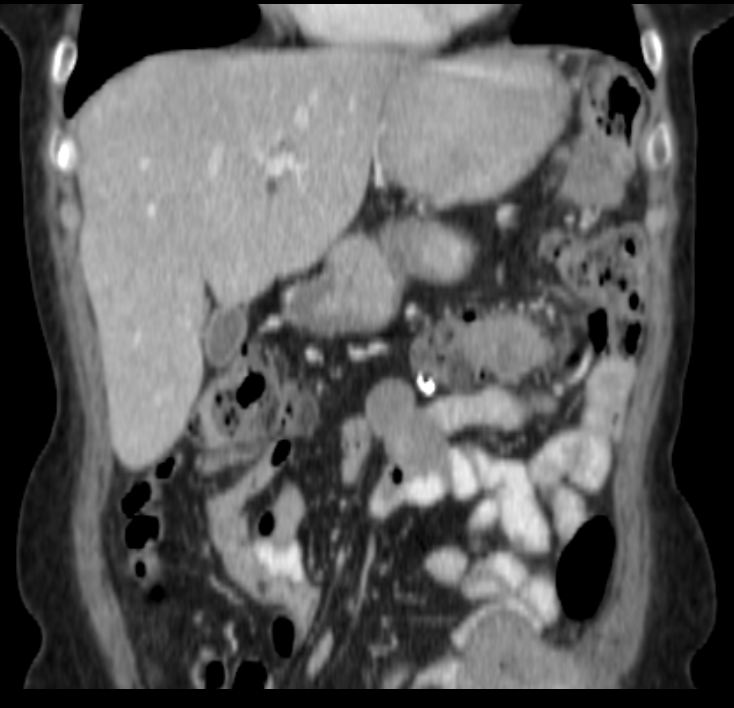

Селезенка размерами 12.5*9.2*10.3 см (34Х). В ее паренхиме множество округлых образований размером до 0.8 см, плотностью 516х. В проекции ворот селезенки определяется нечетко очерченный участок низкой плотности(12Х), с неровными контурами, размером 7.3*7.7*7.4 см,

при контрастировании - гиперваскулярный по периферии.

Подкапсульно у верхнего полюса селезенки образование размером 2.4*1.7 см, у нижнего полюса размером 2.9*3.6 см, гетерогенной структурой, негомогенно усиливающиеся при контрастировании.

По латеральному контуру слепой и восходящей кишки образование мягкотканной плотности, с волнистым четким контуром, размером 2.6*7.2 см, неравномерно усиливающееся после контрастирования.

На границе нисходящего отдела и сигмы образование размером 7.6*6.8 см, прорастающее переднюю брюшную стенку (38Х), так же неравномерно накапливающее контраст.

Заключение: КТ - признаки cr слепой, восходящей кишки; cr сигмы с прорастанием в переднюю брюшную стенку. Mts в селезенку и печень. Кальцинаты в селезенке. Киста правой почки.

Метастазы по брюшине, сальнику -  моё мнение. Откуда - я не знаю. Возможно, первичная опухоль в селезенке (дифференцировать между гемангиосаркомой и метастазом). Но более реально - из яичников или молочных желез. Одни вопросы, поскольку полость таза не вошла в зону сканирования. Изменения в легких - тоже в срезе.